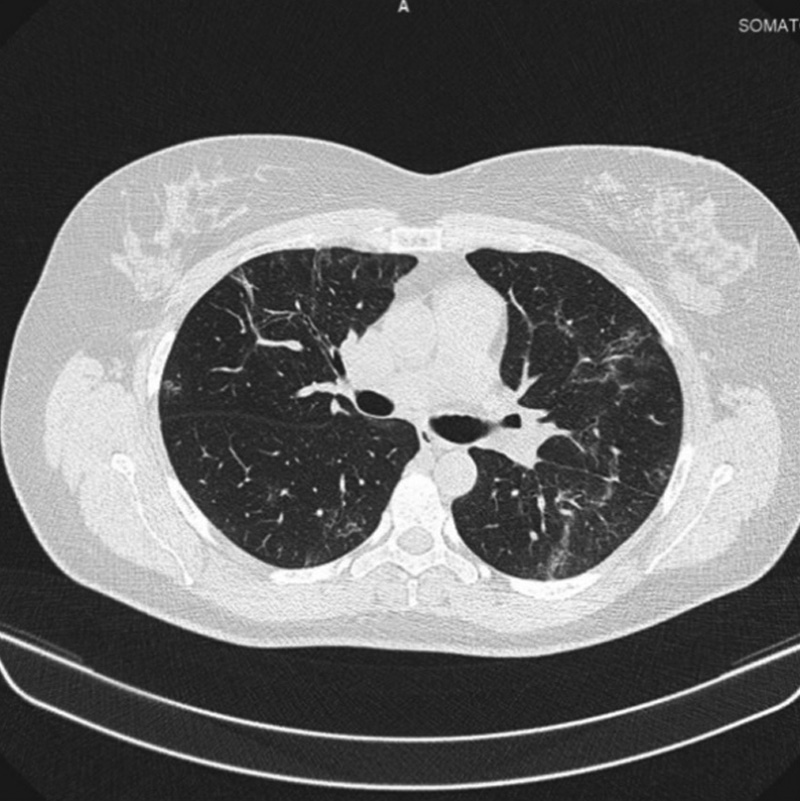

Через 4 мес. после выписки выполнено контрольное КТ ОГК: легкие без очаговых и инфильтративных изменений. С двух сторон определяются участки консолидации легочной ткани. На КТ признаков инфильтративных изменений легких не выявлено, явления пневмофиброза отсутствуют, КТ-картина перенесенной вирусной пневмонии.

Рис. 2. Компьютерная томограмма органов грудной клетки после завершения курсового лечения препаратом бовгиалуронидаза азоксимер

Fig. 2. Computed tomography of the chest after the completion a course of Longidaza

On computed tomography, no signs of infiltrative changes in the lungs and signs of pneumofibrosis, a picture of viral pneumonia, were noted.